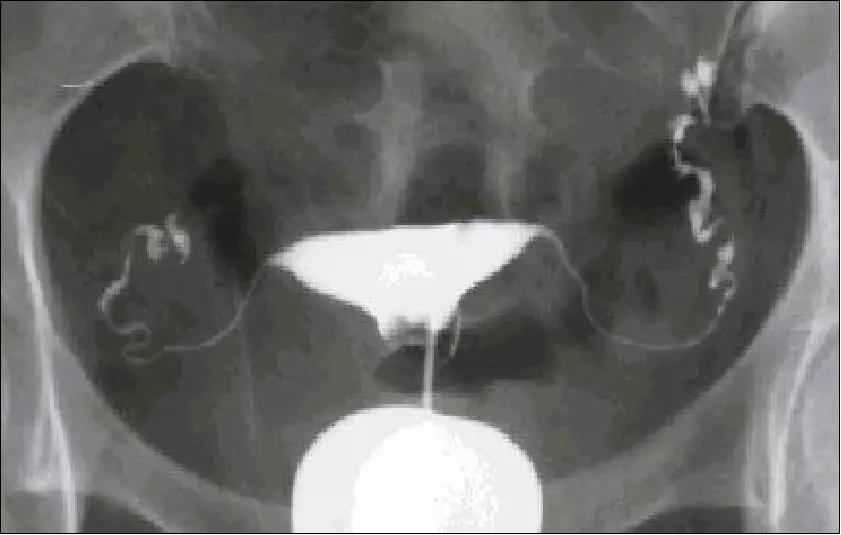

女方:基础性激素测定、盆腔B超、阴道/盆腔感染微生物检查、输卵管通畅检查和排卵监测。